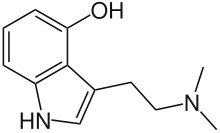

| Bufotenin | Animals, plants, fungi | 5-OH | CH3 | CH3 | 5-hydroxy-N,N-dimethyltryptamine | 487-93-4 |